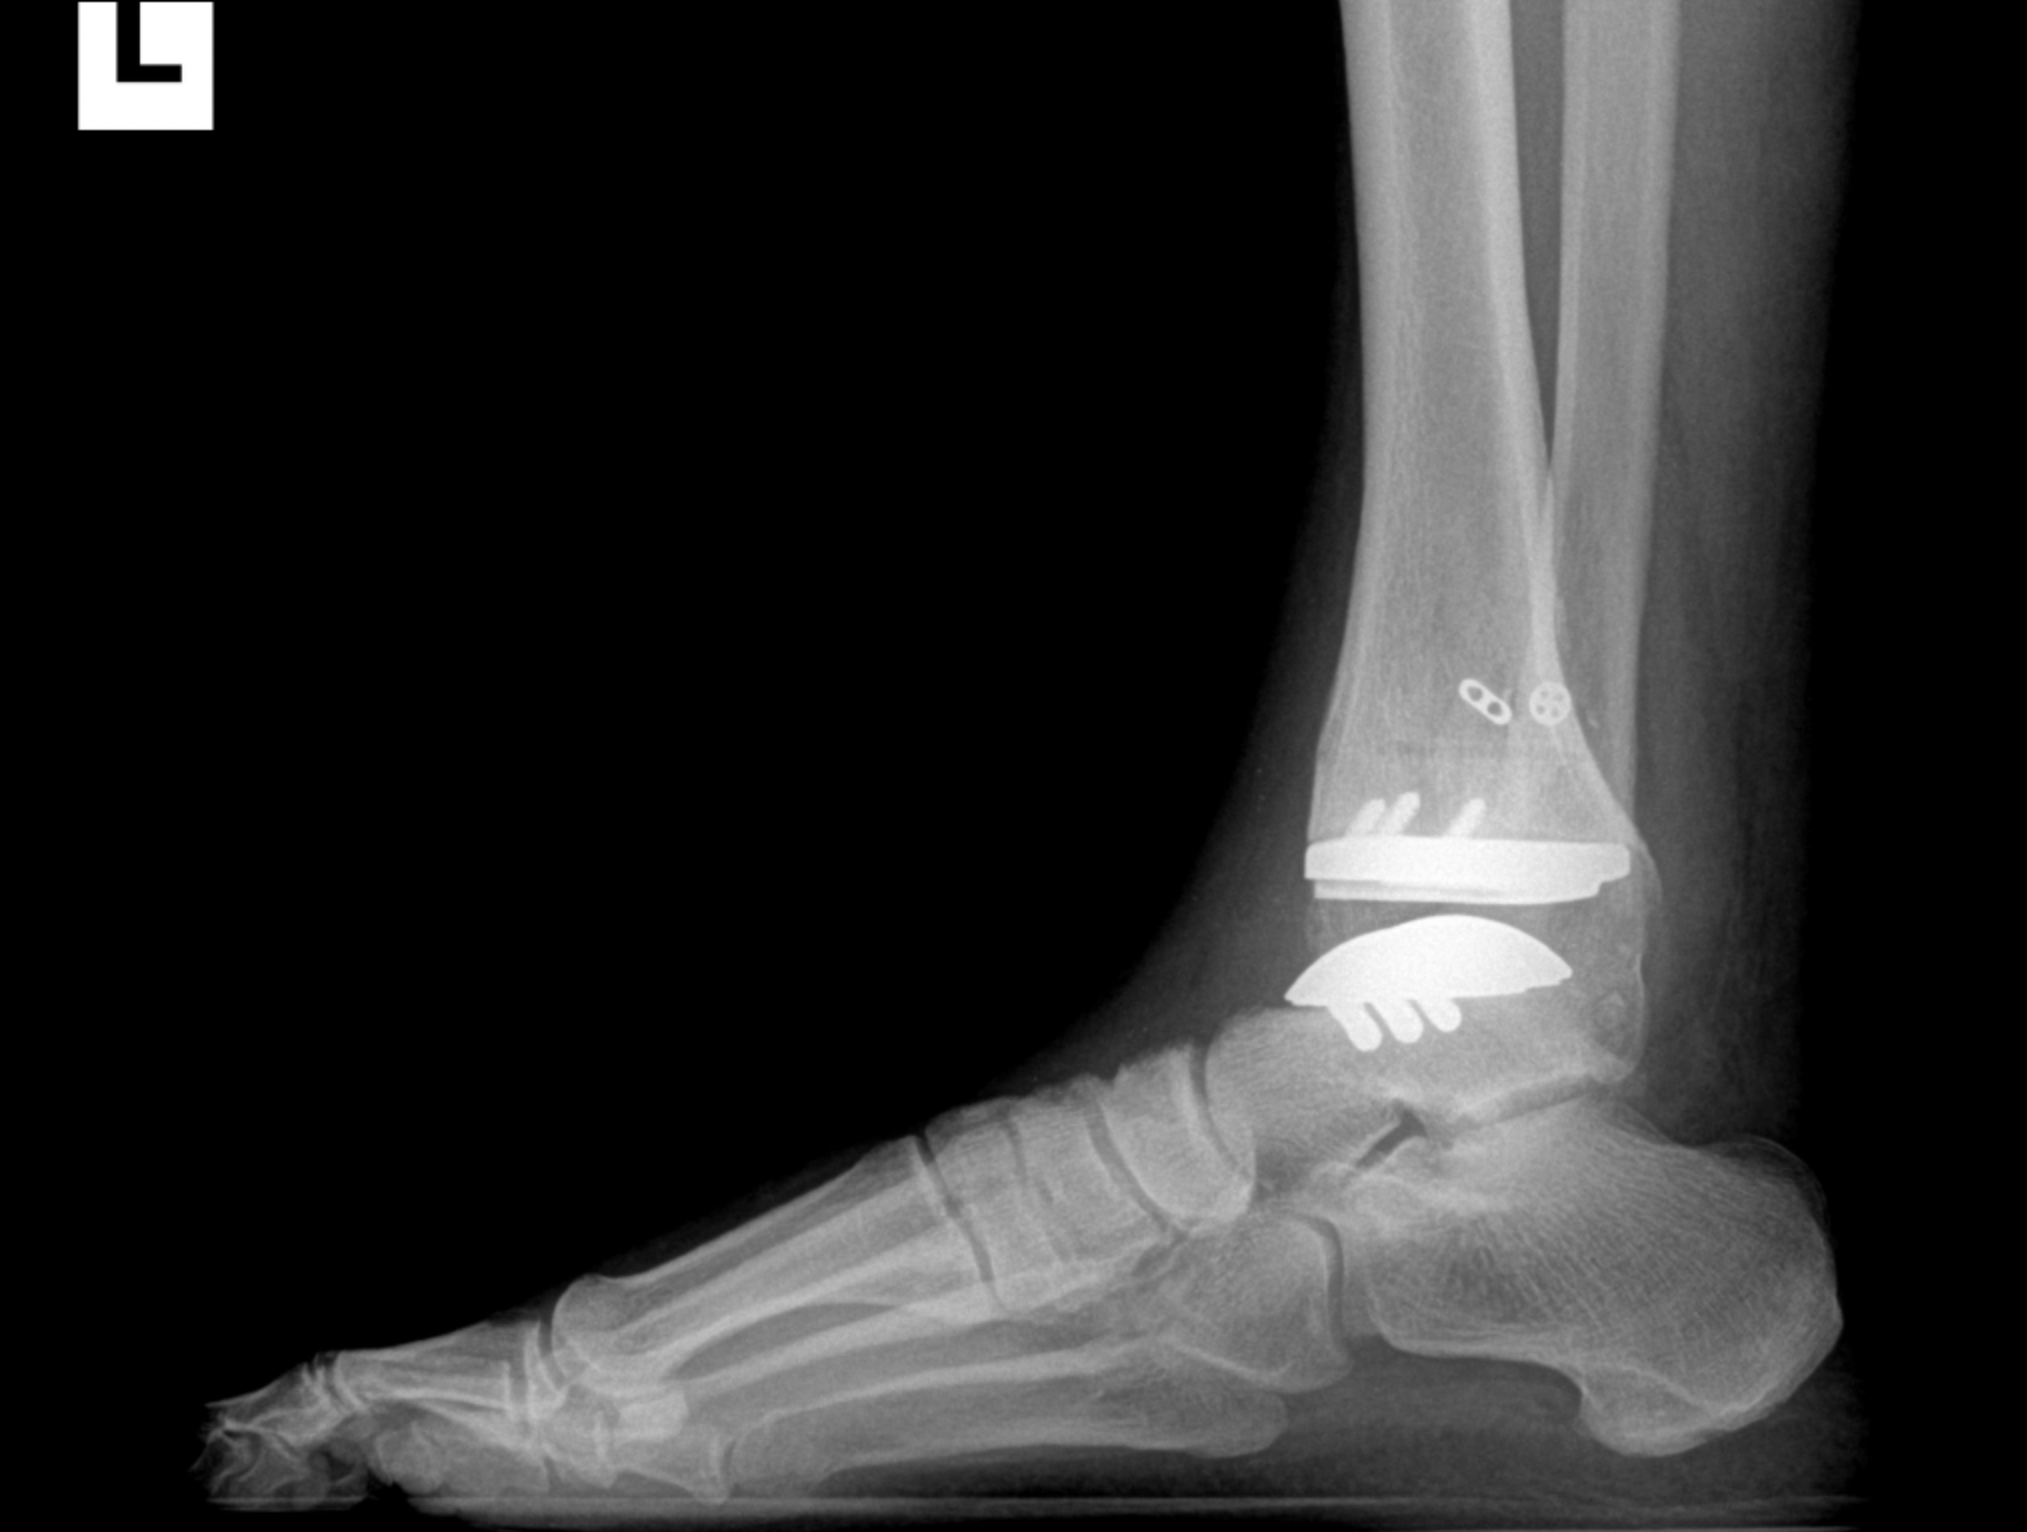

Foot & Ankle Replacement